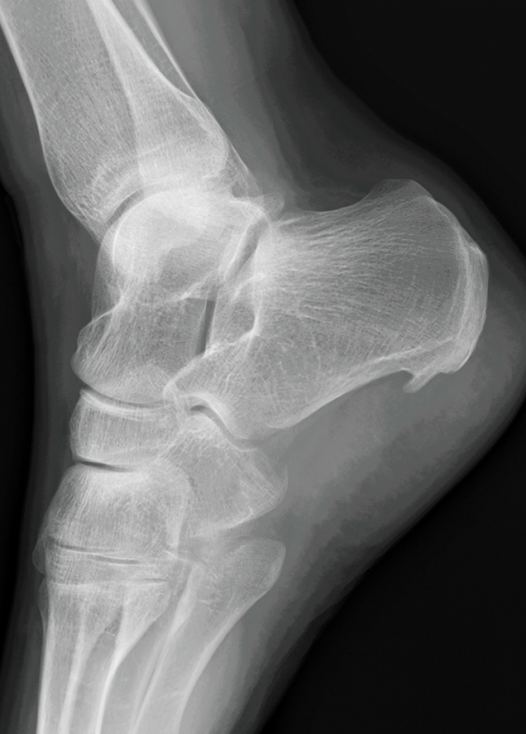

Der Orthopäde wird zunächst eine gründliche Untersuchung durchführen, um die Ursache der Fersenschmerzen zu bestimmen. Dies kann eine körperliche Untersuchung, eine Ultraschalluntersuchung oder eine Röntgenaufnahme beinhalten. Basierend auf den Ergebnissen der Untersuchung kann der Orthopäde verschiedene Behandlungsmöglichkeiten vorschlagen, wie z.B. Physiotherapie, Schmerzmittel, orthopädische Einlagen oder in schweren Fällen eine Operation.